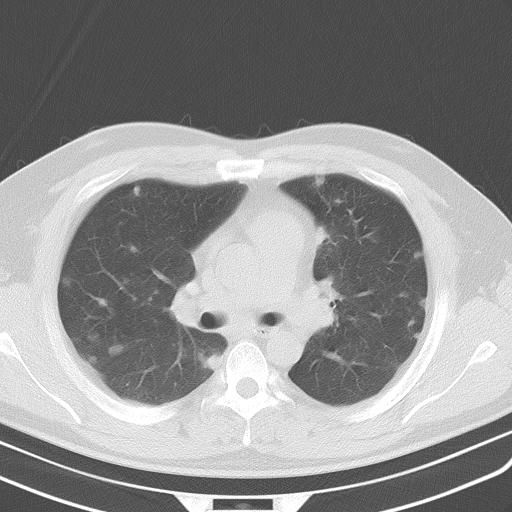

患者男性 35 主因发热咳嗽四天,血象不高,心肺听诊未见异常,无其它病史及传染病接触史。

两肺散在大小不等小结节影,下野较多,纵隔淋巴结增大。考虑:1、慢性血播性肺结核;2、霉菌病?3转移瘤待排。

两肺多发结节,部分病灶边缘不清,且示毛玻璃影。分布特点为沿血管支气管分布。

结合临床考虑;1,炎性肉芽肿性病变;霉菌?过敏性肺炎?2,韦格氏肉芽肿。3,转移瘤。

双肺散在多发类圆形结节灶,边缘较光滑,纵隔淋巴结肿大,考虑转移瘤

淋巴结近呈对称性肿大,肺部多发结节,首先考虑结节病,其次考虑转移瘤。